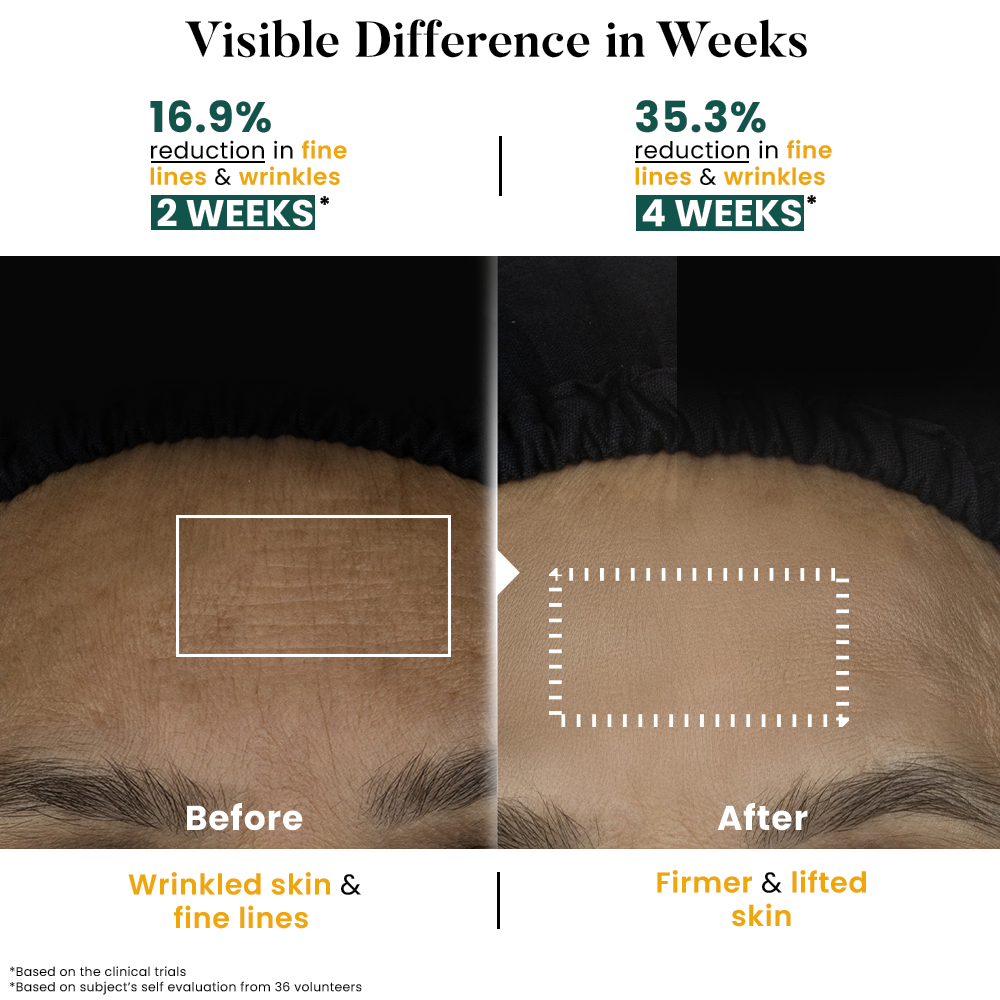

Before

After